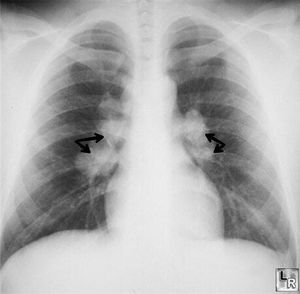

Silicosis is an occupational disease that is a part of group of diseases called pneunoconiosis.It occurs in workers who work in shipbuilding, roofing, and plumbing industries. Silicosis may impair macrophage function which increases the susceptibility to TB and also increases the incidence of primary lung cancer.